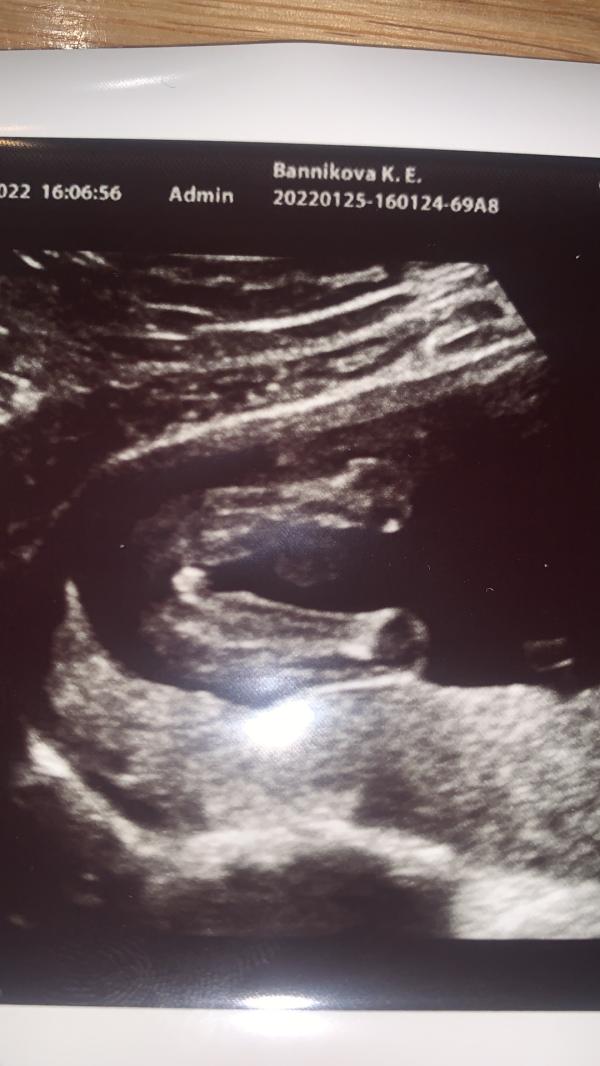

На УЗИ сказали, что будет девочка, но я сомневаюсь

Ходили на узи 16 недель) сказали девчонка)) я приближаю фото мне кажется что то там есть не девчачье🙈

У меня такое же фото с УЗИ, узист мне приблизил и показал полосочки,типо 100% девочка

У меня такое же фото, это девочка